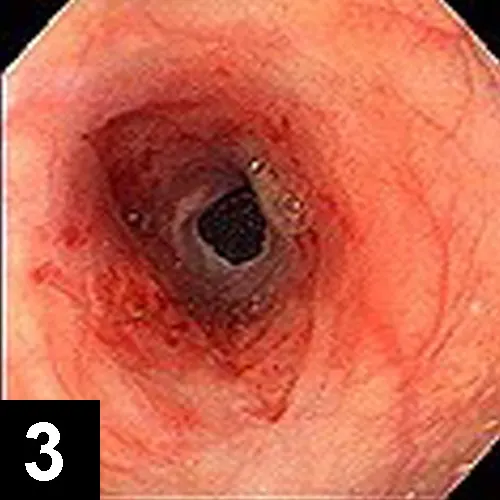

The most likely cause of this abnormality is an intramural esophageal stricture. Unlikely causes for esophageal narrowing include extrinsic extraesophageal compression from neoplasia or inflammation, vascular ring anomaly, presence of an esophageal foreign body, or esophageal neoplasia. Endoscopy was done to delineate the obstruction and to perform therapeutic esophageal dilatation. Figure 2 shows the esophageal narrowing at the thoracic inlet. Figure 3 shows the esophagus following a balloon dilatation procedure.

Figure 2. Endoscopic view showing a benign focal esophageal stricture secondary to a doxycycline tablet in a cat